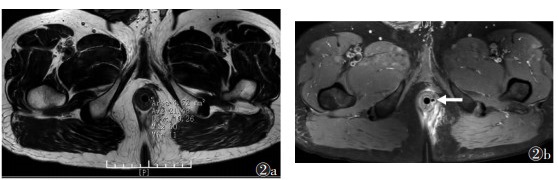

湿热下注证的主瘘管T2WI信号强度明显高于正虚邪恋证(P<0.01,图 1,2)。2组主管的内口位置、深度、长径及支管T2WI信号强度比较,差异均无统计学意义(均P > 0.05)。

| 图 2 男,34岁,复杂性肛瘘。正虚邪恋证 图2a T2WI上肛瘘位置测量信号强度为21.4 图2b 箭头为PDWI上瘘管位置 |